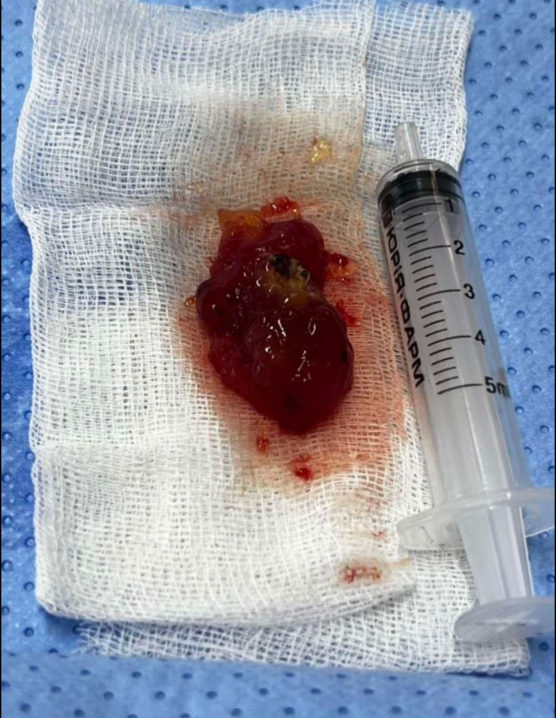

Життя буковинки врятували кардіохірурги Чернівецької обласної клінічної лікарні. Під час складної операції лікарі видалили з її серця рідкісну пухлину – міксому лівого передсердя, розміром 2,5×5 см.

"У цьому випадку пухлина була особливо загрозливою, оскільки мала желеподібну структуру і не була капсульованою. У будь-яку мить могла фрагментуватися та спричинити інфаркт або інсульт. Такий стан становить серйозну небезпеку для життя, – розповідає лікар-кардіохірург ОКНП «Чернівецька обласна клінічна лікарня» Андрій Перепелюк. – Завдяки злагодженій роботі команди лікарів вдалося своєчасно усунути загрозу й врятувати життя молодій жінці".